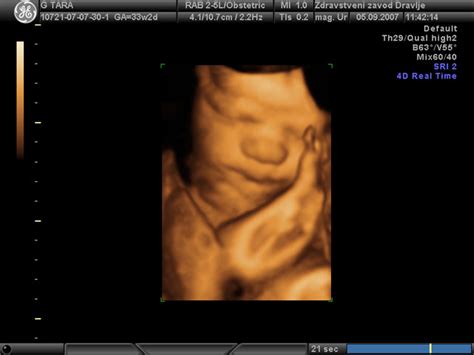

3D/4D Prikaz Ploda

Čeprav 3D/4D ultrazvok v prvi vrsti služi za vizualizacijo plodovih značilnosti in krepitev čustvene povezave med starši in otrokom, lahko v določenih primerih ponudi tudi dodatne diagnostične informacije. Z možnostjo prikaza v treh dimenzijah je mogoče bolje oceniti nekatere zunanje anatomske strukture ali nepravilnosti. V Ginekološki ambulanti Rodna Kranj omogočamo 3D/4D prikaz ploda med 25. in 30. tednom nosečnosti, kar omogoča staršem edinstven vpogled v videz njihovega otroka.